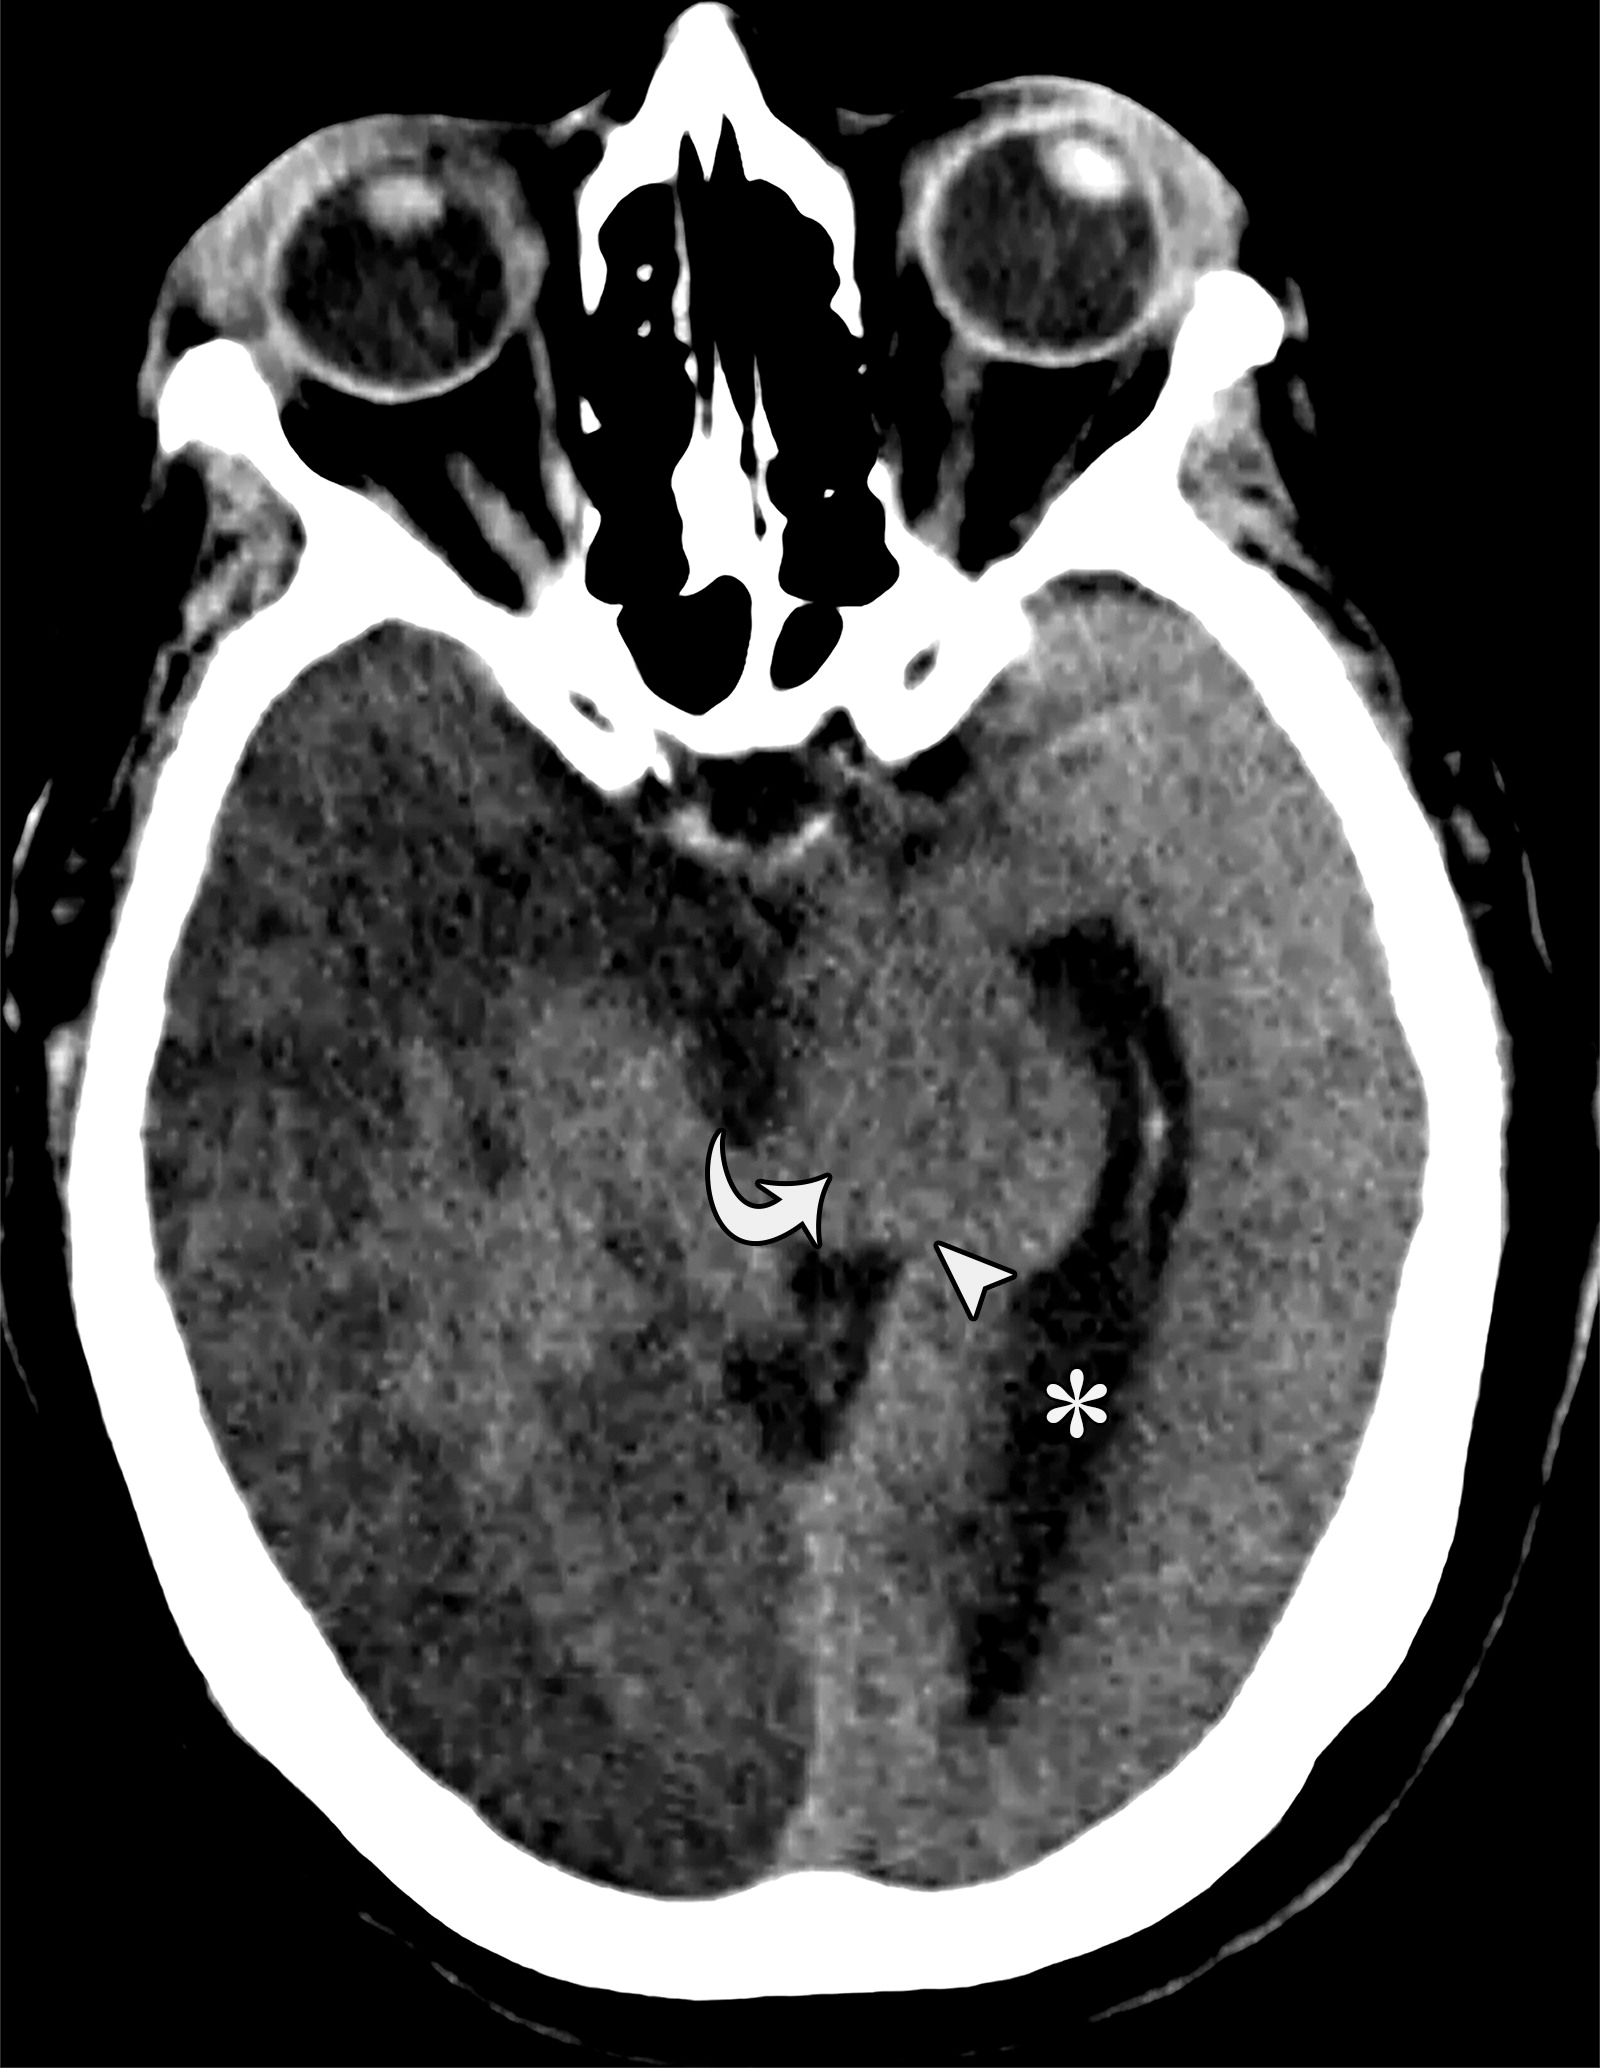

35092bcf5effd8e2414c408677ab3fb1.jpeg

下降性小脑幕裂孔疝。64岁男性,缺血性心脏病病史,由于卒中出现突发的神经系统恶化。继发于脑水肿的下降性小脑幕裂孔疝。在中脑水平的轴位平扫CT示中脑向左移位及旋转(白色弯曲箭头),四叠板向左侧移位(白色短箭头),中脑周围池的闭塞。以及左侧侧脑室的扩张(*)